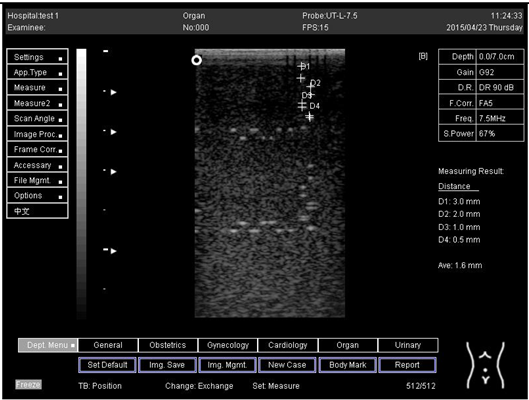

9.0 Axial resolution

Biomimetics 07 00130 i009

D1 = 5.0

D2 = 3.9

D3 = 3.0

D4 = 2.2